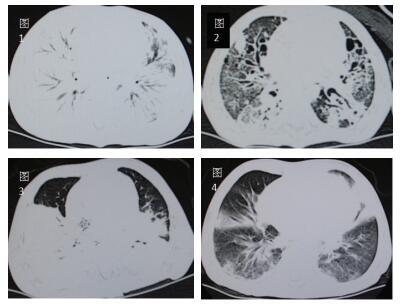

初期表现为单侧节段性实变为主(3/9),双侧散在片状影或大片融合灶(6/9),伴有部分肺气肿。快速进展至双侧大片肺实变(5/9))或者“白肺”(4/9),伴胸腔积液或者气胸、纵隔气肿。恢复期多见背段、双下肺散在片状影残留(7/9),部分发展为肺纤维化及肺坏死灶(2/9)。典型影像学改变见下图。

| 图 1 图 1、2分别示例7急性期,两肺几乎完全实变;恢复期,肺纤维化及坏死空洞图。图 3、4分别示例4急性期,背段大面积融合实变伴肺气肿;恢复期,树芽状增生,毛玻璃样变。 |